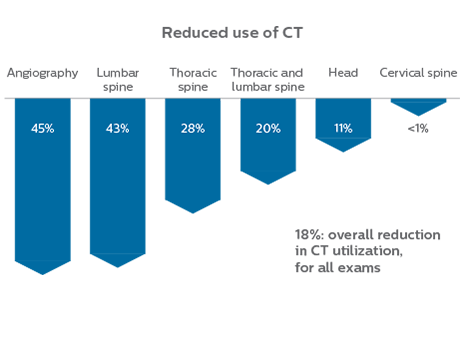

When neurological emergencies require diagnostic imaging, common practice in the ED has been to perform CT rather than MRI, even when MRI could potentially produce more informative diagnostic images of spinal cord damage, disc protrusions, soft tissue injuries, and stroke pre-cursors. [1,2] The main reason is that timing is essential in emergency cases, and CT is generally faster than MRI. The St. Joseph’s Hospital and Medical Center is now challenging this paradigm by offering rapid MRI scans within its Neurologic ED and seeing that it helps them make a richer diagnosis.

Since 2012, St. Joseph’s Hospital and Medical Center in Phoenix, Arizona, USA, has had an ED dedicated to neurological patients. In 2015, John Karis, MD, of the Barrow Neurological Institute at St Joseph’s spearheaded a project to place an MRI system in the Neuro ED. He stressed the added prognostic value of having an emergency MRI, and the importance of reducing radiation doses, particularly in patients for whom a CT scan was not the optimal test.

efficient as CT for referring physicians, then physicians would probably prefer MRI over CT in part of the cases. Reducing the number of CT scans for patients less than 40 years of age without significant acute findings, such as acute stroke, was also a main reason for introducing MRI into the ED. “MRI is a better test for identifying soft tissue abnormalities in the brain. What really influenced the decision on the administrative side, was the total radiation dose received by ED patients, and how this could be reduced by introducing MRI in the ED”.

“In the past, CT scans were performed because of their availability and rapid turnaround time” Dr. Karis argues, “but if an MRI could be as efficient as CT for referring physicians, then physicians would probably prefer MRI over CT in part of the cases. Reducing the number of CT scans for patients less than 40 years of age without significant acute findings, such as acute stroke, was also a main reason for introducing MRI into the ED. “MRI is a better test for identifying soft tissue abnormalities in the brain. What really influenced the decision on the administrative side, was the total radiation dose received by ED patients, and how this could be reduced by introducing MRI in the ED”.

Since 2012, St. Joseph’s Hospital and Medical Center in Phoenix, Arizona, USA, has had an ED dedicated to neurological patients. In 2015, John Karis, MD, of the Barrow Neurological Institute at St Joseph’s spearheaded a project to place an MRI system in the Neuro ED. He stressed the added prognostic value of having an emergency MRI, and the importance of reducing radiation doses, particularly in patients for whom a CT scan was not the optimal test.

Changing established behaviors

The transition away from a predominantly CT-based ED began by educating physicians about the advantages of MRI in the emergency setting, when to use MRI, and the importance of targeted exams instead of broader, non-targeted exams. Some resistance to the change was anticipated, as it was disrupting established routines, so a reasonable amount of time was planned for educating referrers, neuroradiologists and neurosurgeons, as well as residents and fellows. However, less time than anticipated was needed: all involved were already familiar with MRI and, more importantly, they were easily persuaded on learning about the 10-minute exam duration with MRI.

At St. Joseph’s Hospital and Medical Center, the dedicated MRI system in the ED has been shown to efficiently provide high quality MR images that assist physicians in making informed decisions on patient diagnoses and take a more definitive decision on follow-up. The decision to have a dedicated ED MRI has resulted in rapid patient turnaround, efficient patient management, and substantial reductions in radiation dose.